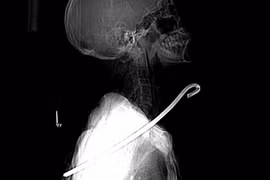

Cứu sống người đàn ông bị cây sắt đâm xuyên cổ

(GLO)- Êkip bác sĩ Bệnh viện Đa khoa tỉnh Hà Tĩnh vừa cứu sống ông V.C.Đ. (SN 1956, trú xã Kỳ Tiến, huyện Kỳ Anh, tỉnh Hà Tĩnh) bị cây sắt dài khoảng 30 cm đâm xuyên cổ.